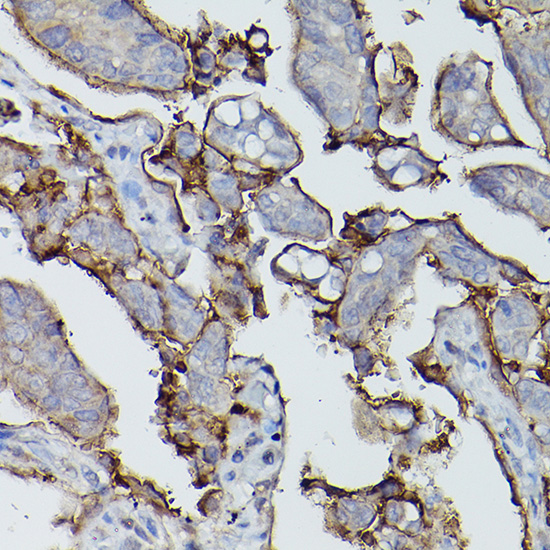

Immunohistochemistry of paraffin-embedded human lung cancer using Alkaline Phosphatase (ALPL) Rabbit pAb.